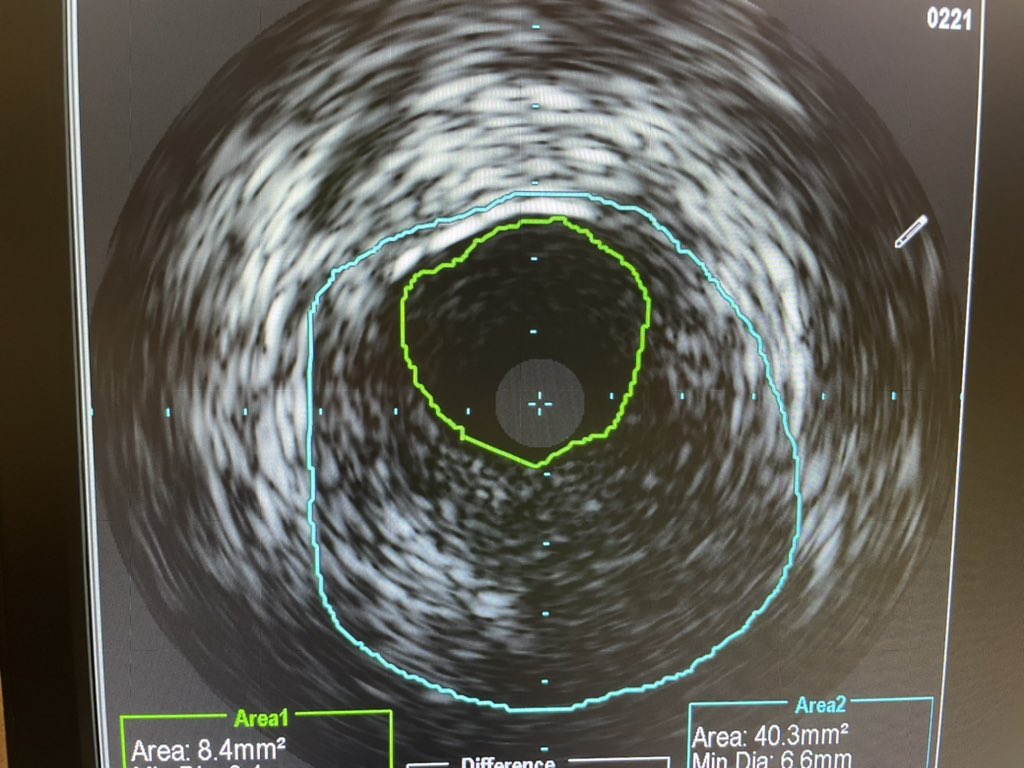

Dr Chirdeep Patel our MCS fellow did this case skin to skin. Surgical turndown Critical LM with CTO RCA. IVUS guided DK Crush with Impella in CKD patient. Total contrast 48cc. He used CO2 angio for large bore access and completion angio. Awesome to see such expertise.